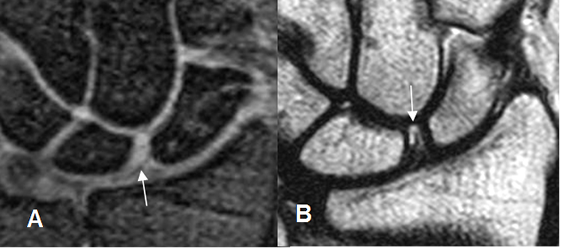

Fig 71. Ruptura del ligamento escafosemilunar.

A: RM coronal en GE. Aumento del espacio y laxitud del ligamento escafosemilunar, por ruptura.

B: RM coronal en GE. Escaso líquido en el espacio mediocarpiano, signo indirecto de ruptura del ligamento escafosemilunar.